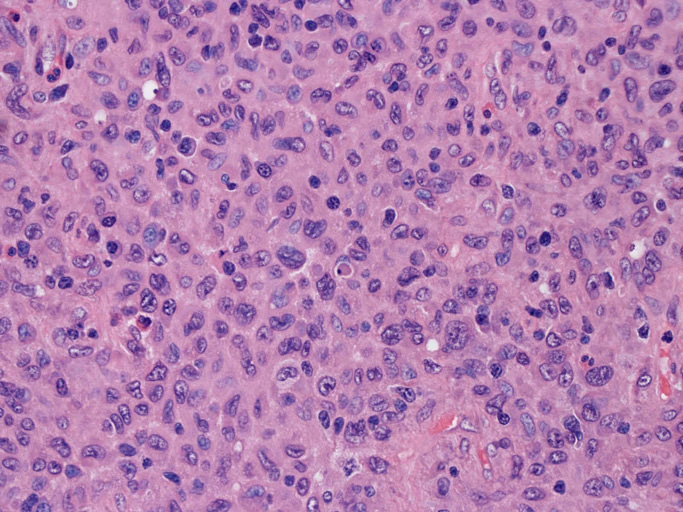

LCSの病理組織所見

Langerhans cell histiocytosisの高悪性度 variantで明らかな悪性像を示すLangerhans cellの腫瘍性増殖と定義される(WHO, 2008)

大型細胞の増殖よりなる腫瘍。縦溝,しわ,切れ込みのある核をもった大型細胞も出現する。クロマチンは顆粒状で核小体も明瞭である。核分裂は >50/10hpfと多い。eosinophilsは少ない。壊死が多発することがある。未分化ないし低分化な細胞像, 組織所見のため鑑別診断は多岐にわたり、的確な免疫染色を行う必要がある。

皮膚に異型細胞の浸潤がみられる。異型細胞は表皮内に浸潤するほか、表皮真皮境界部, 真皮, 皮下脂肪組織にもびまん, 結節様の浸潤所見を示す。血管周囲に浸潤、集蔟する所見も多く見られる。 増殖浸潤細胞の核には類円形や腎臓形, またはへこみ, 切れ込み, 溝などを有する多型な核が認められる。クロマチンは粗でvesicularな核が多い。核小体の明らかな核もある。好エオジン性の核内封入体様構造も少数に見られた。mitosisは容易に認められる。hyperchromaticな多型核, bizzarreな細胞が高頻度に認められ異型度は高いと考えられる。細胞質は境界不明瞭, 淡明または泡沫様の 好エオジン性胞体である。

免疫染色 浸潤細胞はCD1a+, S100+, Langerin+, HLA-DR+, CD4+, CD45+, CD68+. MIB-1 index:24.4%